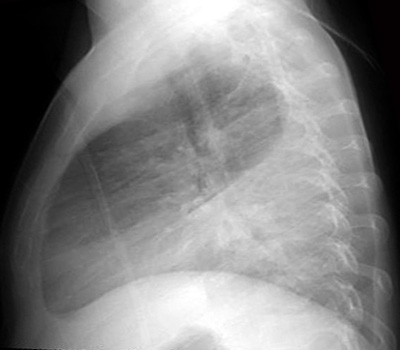

PA and LAT CXR demonstrates a left lower lobe consolidation, representing pneumonia.

Also note the meniscus in the left costophrenic angle indicating a parapneumonic left pleural effusion.